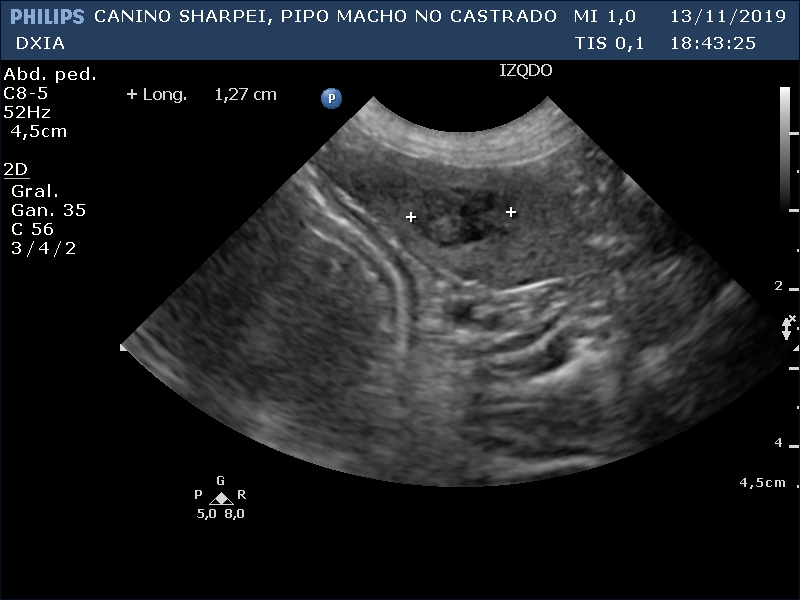

Nódulo en bazo de 1,27cm de diámetro heterogéneo compatible con posible neoformación/metástasis, hematoma/granuloma, …

Comentario imágenes A y B: Comparativa Asas ID normal con asa alterada donde se observa aumento de la pared (engrosamiento) con pérdida de estructura en capas.

Neoformación en ID de la que se realiza PAF ecoguiada.